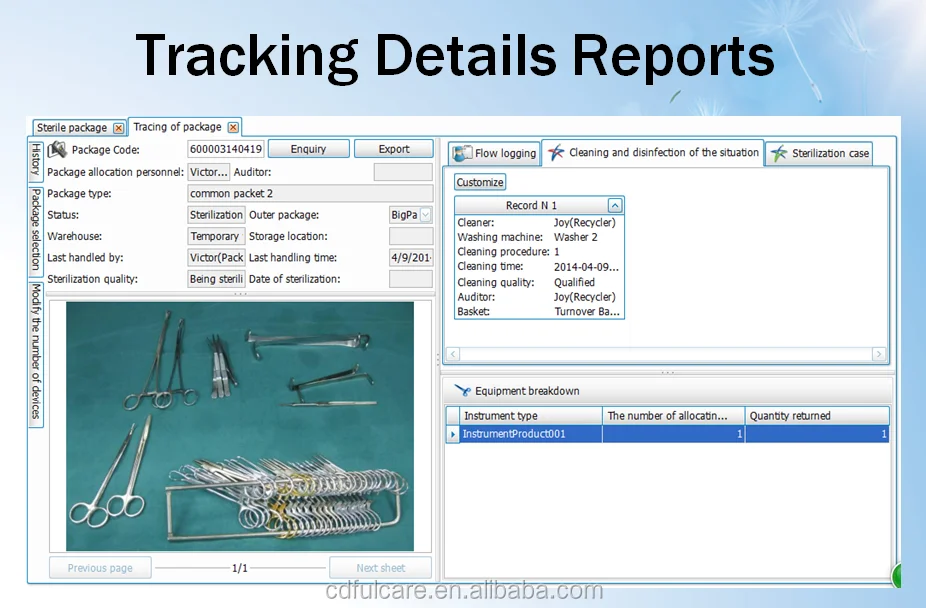

Easy tracking system for hospital CSSD sterilization

- Category:

- Supplier: Chengdu,Fulcare,Trading,Co.,Ltd.,[Sichuan,China]Chengdu

RUB 77.94

In Stock

Hospital CSSD instrument management software

- Category:

- Supplier: Chengdu,Fulcare,Trading,Co.,Ltd.,[Sichuan,China]Chengdu

RUB 77.94 - RUB 779.34

In Stock